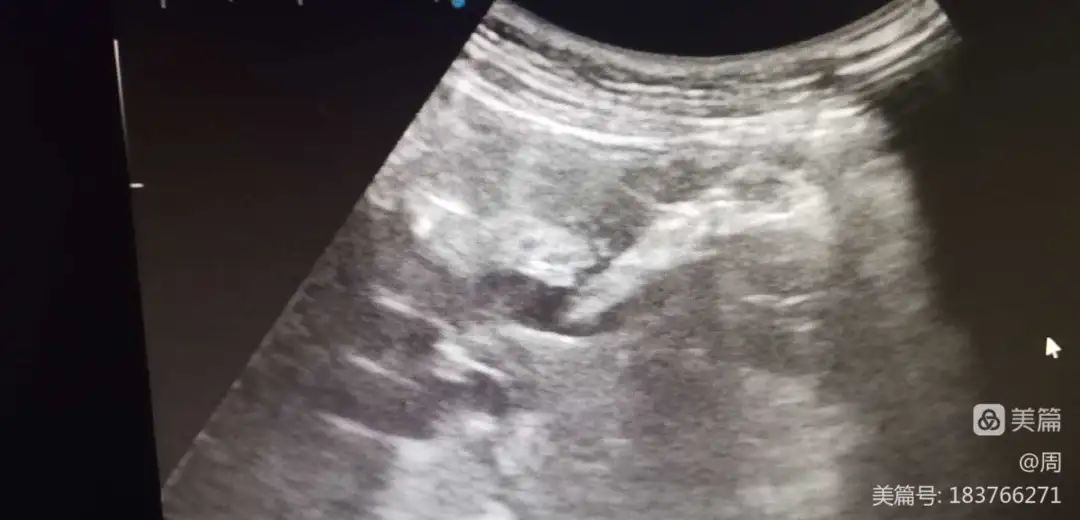

超声科主治医师周晓霞为病人设计穿刺路径。

置入引流管

成功引流出胆汁